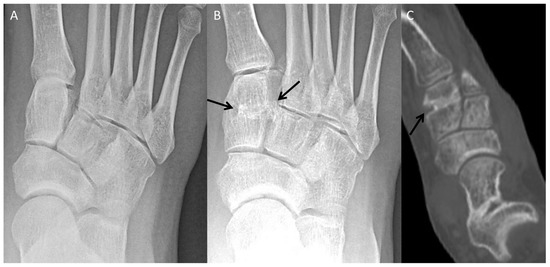

4.1. Accessory Navicular Resection